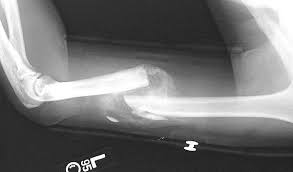

Krč 95%, ka pirms 2 nedēļām salauzu kājai mazo pirkstu sāp nereāli, kā kustina tā sāp, nedod dievs katkur bikses velkot ieķerās, liekās vispār pirksts nolūzīs da galam no sāpēm, pie ārsta negāju, mutere teica, ka viņi tāpat neko viņam neizdarīs, jāgaida kad sadzīs, poh tā arī 2 nedēļas kliboju apkārt tā arī nekas nemainās, šādā situācijā jāiet pie ārsta vai pohuj ar laiku pāries?

Ir vērts aiziet, viņi var ielikt vismaz taisni atpakaļ (tho pēc 2ned tas visticamāk nozīmē, ka viņi ielauzīs taisni)

Lietas labá viņš var sadzīt, bet var saaugt nepareizi. Man ļoti palīdzēja zirga smērs pret sāpēm. Nahuj naktīs nevarēju pagulēt, kad no čoma dabuja, pēc 5min sajūta bija, ka nekas man nebija lauzsts

Tas ir ja vispār tev ir lauzsts, varbūt tikai satriekts kājas pirksts, ko tu zini? Huh?!?

Salauz velreiz, lai saaugtu pareizi, savādāk būs līks pirkstiņš. Es salauzu vienreiz pirkstam trešo falangu un pie ārasta nebiju aizgājis vairāk kā nedēļu un tad aizmacu, ieģepsēja un saauga pareizi, savādāk būtu nedaudz līks pirksts